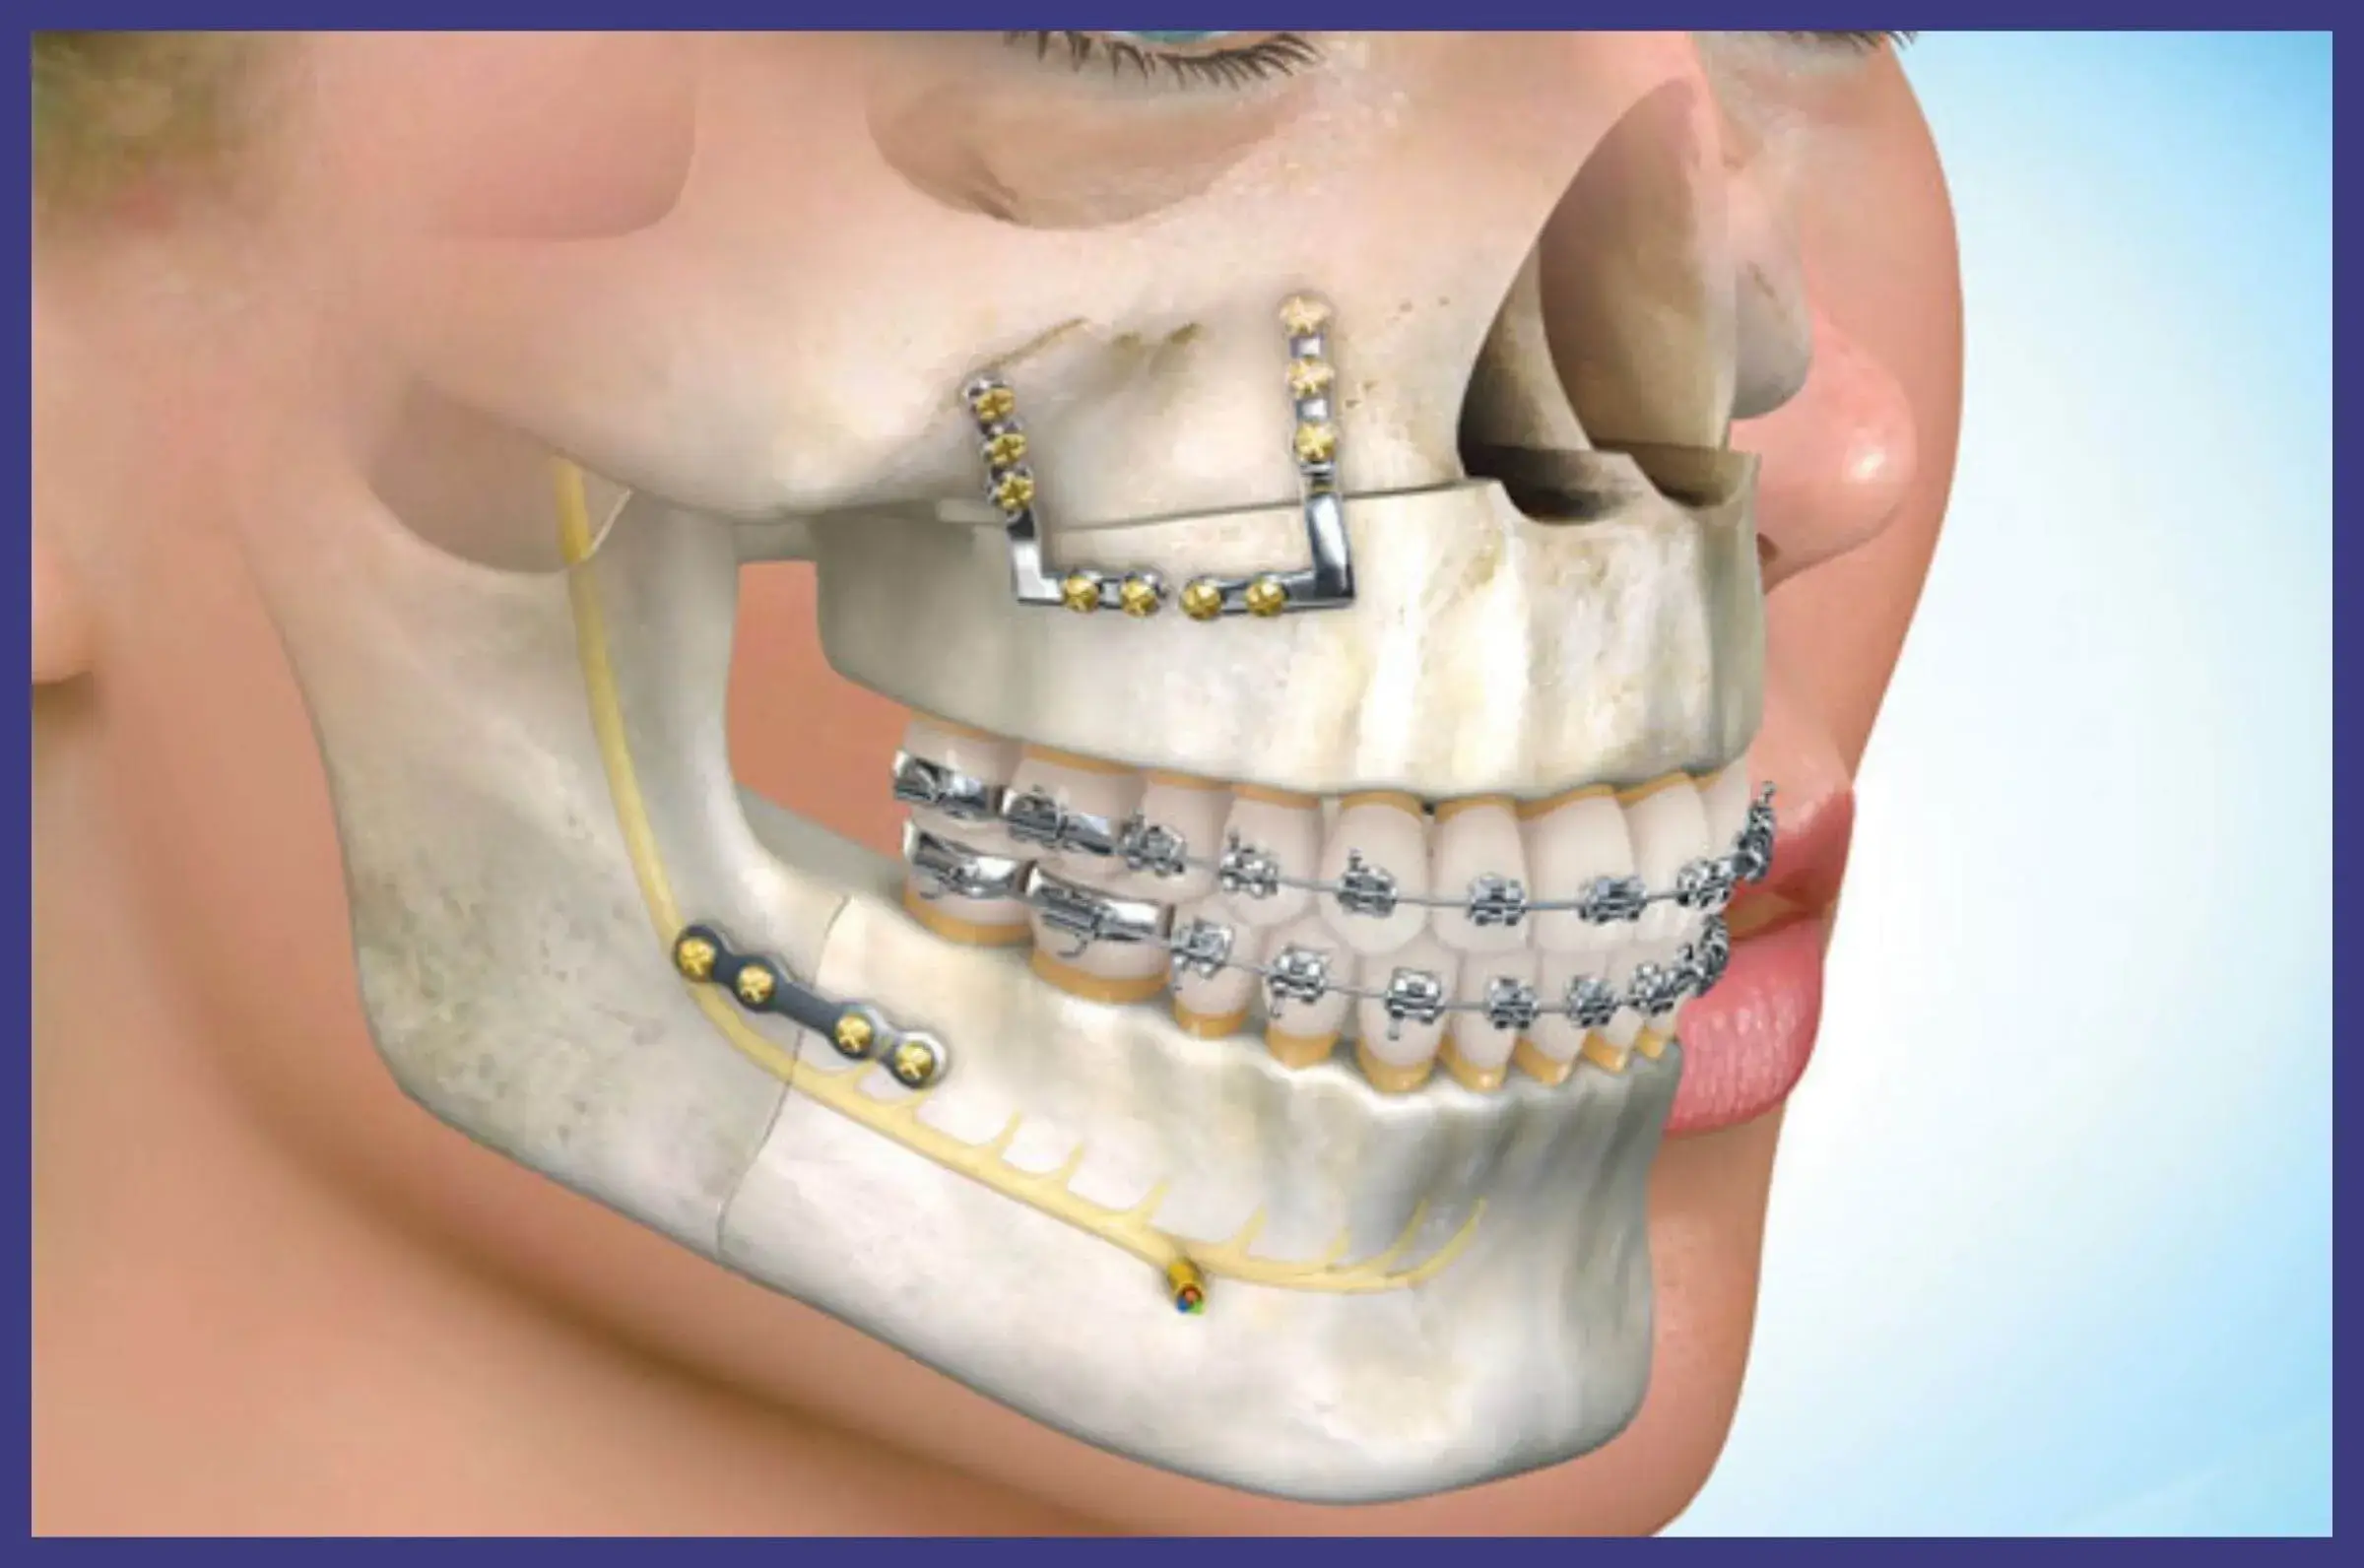

همراهان گرامی دکتر پیج، سلام. این بار در حوزه دندانپزشکی بر آن شدیم تا تنی چند از بهترین جراح فک و صورت در تهران را به شما معرفی کنیم. جراحی های این حوزه به سبب اصلاح بسیاری از ناهنجاریهای اسکلتی و دندانی جزئی و اساسی از جمله نامرتبی فک و دندانها انجام میشود. متخصص جراحی فک دهان صورت جراحی است که طیف وسیعی از بیماریها، صدمات و نقوص سر و صورت و فک و گردن و طاق جمجمه، بافت نرم و … را درمان می کند. خدماتی که جراح دهان و فک و صورت می تواند به شما ارائه بدهد شامل ایمپلنت (کاشت دندان)، جراحی های داخل دهانی، جراحی بینی، پلک و صورت، تصحیح خط خنده و جراحی دندان های نهفته و عقل می باشد.

اگر مشکلی در دندانها، فکها یا استخوانها و بافتهای صورت دارید که باعث ناراحتی شما میشود و شما را از انجام فعالیتهای عادی باز میدارد، ممکن است لازم باشد برای اصلاح ناهنجاری، تسکین درد، و بازگشت به زندگی عادی به یک متخصص جراحی دهان و فک و صورت مراجعه کنید.

جراحان فک و صورت، متخصصانی هستند که آموزش دیده اند تا انواع مختلفی از بیماری ها و آسیب هایی را که سر، گردن، دهان، فک و صورت را تحت تاثیر قرار می دهند، درمان کنند.

جراح فک و صورت چه می کند؟

جراحان فک و صورت در درمان مشکلات و بیماری های مربوط به ناحیه سر و گردن تخصص دارند. بیماری هایی از جمله:

به طور کلی جراحان فک و صورت برای اصلاح مشکلات یا ایجاد تغییرات زیبایی عمل جراحی انجام می دهند. این جراحی ها عموماً روش های سرپایی هستند. احتمالا لازم باشد دوباره جراح خود را ببینید تا روند بهبودی شما تحت نظر قرار گیرد.

·جراحی ترمیمی

این جراحان می توانند استخوان ها را بتراشند، مفاصل را دوباره تنظیم کنند یا حتی به بازسازی حفره های چشمی شکسته کمک کنند. اگر صورت یا فک شما شکسته یا نامرتب باشد، جراحی ترمیمی بسیار کمک کننده است.

·مشکلات اسکلتی

اکثر جراحان فک و صورت تا حدی می توانند به اصلاح مشکلات اسکلتی مانند نامرتب بودن فک ها کمک کنند. اگر درد مزمن مفصل گیجگاهی فکی که به عنوان TMJ شناخته می شود دارید، ممکن است دندانپزشک شما را به جراح فک و صورت ارجاع دهد.